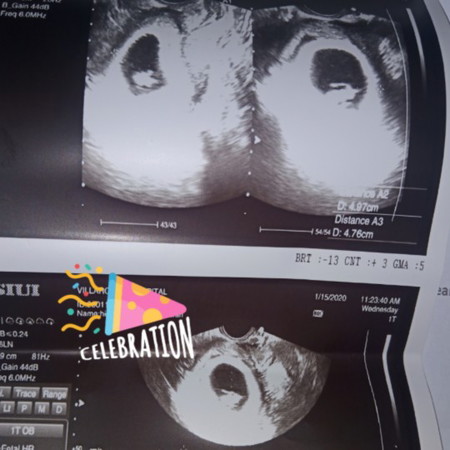

Hi mga momsh! Ask ko lang po kung normal ba yung itsura ni baby? Kase hindi ko po mahanap yung ulo nya at kung ano yung parang buntot. 8weeks and 3days na po ako. Thanyou

Tingnan mo po yung generated report or diagnosis usually sa pinakababa ara malaman kung normal ba si baby. Saka sa 8 weeks di pa talaga sya masyado makikita lalo na kung malabo yung ultrasound.